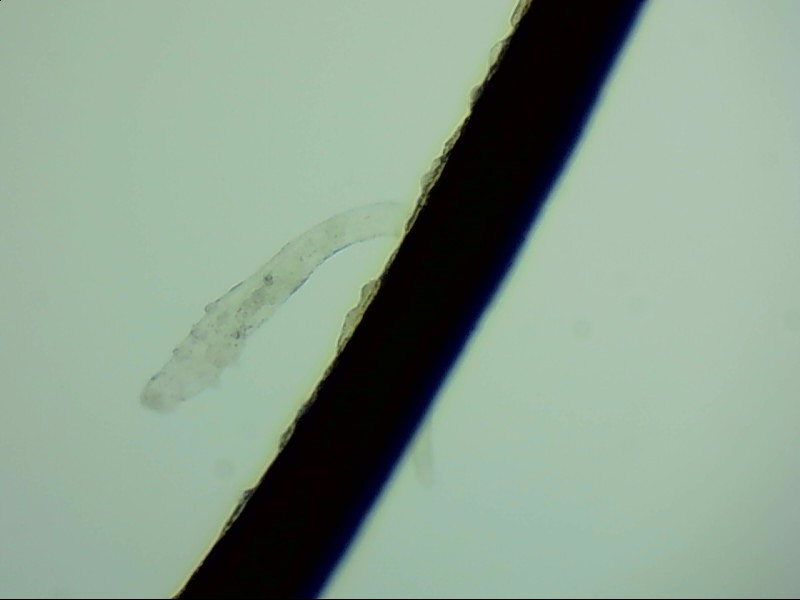

小張是一位程序員,長時間對著電腦,感覺眼干、有異物感在所難免。最近他除了眼干、難受,還發(fā)現(xiàn)眼睛發(fā)癢,掉落的睫毛上還會帶著絲狀的分泌物。剛發(fā)現(xiàn)時小張并沒有放在心上,但當(dāng)他在屏幕上看到睫毛上的螨蟲時,他的心里一陣后怕,“原來我的睫毛上長著這么可怕的東西。”

螨蟲怎么會爬到睫毛里?廈門眼科中心蠕形螨性瞼緣炎門診張麗穎博士后介紹,人體螨蟲主要有兩種,一種是皮脂螨,主要寄生于皮脂腺和瞼板腺內(nèi);另一種是蠕形螨,“住”在睫毛毛囊里,晚上從毛囊里爬出來,白天躲在毛囊里產(chǎn)卵。

據(jù)介紹,這種疾病確診主要通過觀察睫毛里的螨蟲數(shù)量聯(lián)合瞼緣及眼表情況共同診斷。一般而言,如果12根睫毛里,有2條或是超過2條的螨蟲就可以被確診。如果檢查確實發(fā)現(xiàn)較多的蠕形螨感染,建議加上抗螨治療。張麗穎說,發(fā)現(xiàn)眼睛干澀、發(fā)癢,不要自行用藥,建議到醫(yī)院就診。如果長期反復(fù)多發(fā)霰粒腫,要考慮是否存在蠕形螨感染。